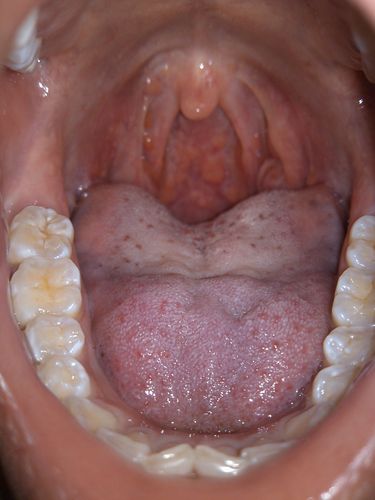

扁桃体上有透明水泡

扁桃体上有透明水泡,扁桃体上有水泡

急性扁桃体炎

正常人的扁桃体图片

帮我看看我这个扁桃体是不是该割掉啊

扁桃体上有水泡

扁桃体上有水泡图片

扁桃体上有溃疡图片

扁桃体发炎起泡图片

扁桃体发炎长泡图片

扁桃体长泡的图片大全

扁桃体化脓

扁桃体发炎

扁桃体角化症